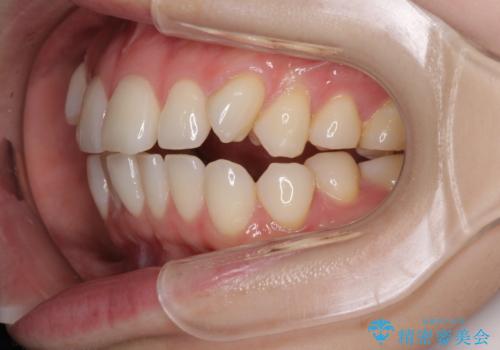

- 前歯のデコボコや八重歯の様になっていることを気にして来院された患者様です。

犬歯捻れて前方に飛び出しており、下顎前歯もそれに沿うようにデコボコとなっていました。

IPR(歯と歯の間を削る処置)によりスペースを獲得して上下顎前歯のデコボコを改善し、前歯が前方に突出しないように設定した上で、インビザラインにて矯正治療を行うこととしました。